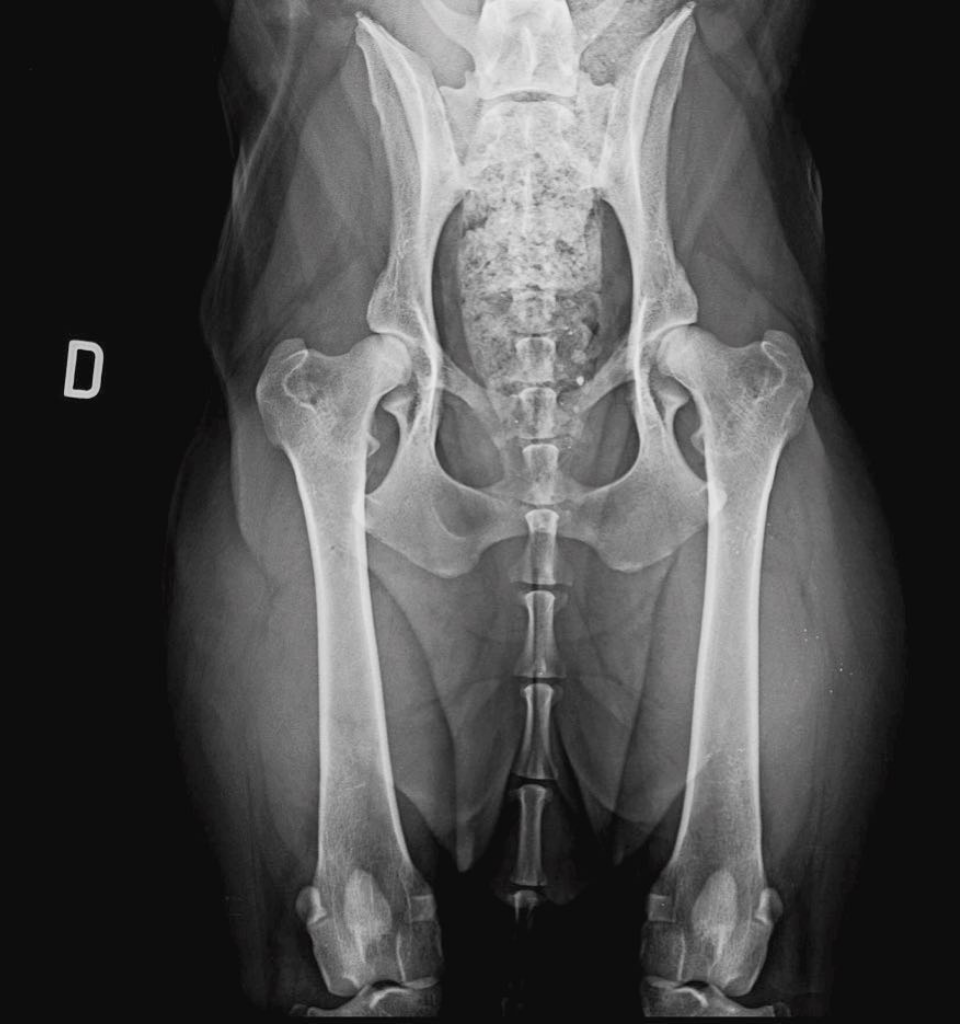

- Lo studio radiografico preventivo di base comprende una o più proiezioni del bacino e almeno una radiografia per ciascun gomito. Nei casi in cui sia necessario un approfondimento più accurato, lo studio può includere fino a quattro proiezioni del bacino (ventro-dorsale standard, ventro-dorsale a rana, proiezione DAR e proiezione distratta) e quattro radiografie dei gomiti, con proiezioni medio-laterali e antero-posteriori per ciascun lato.

- Per la lettura ufficiale della displasia dell’anca sono obbligatorie una radiografia in proiezione ventro-dorsale standard, mentre per la displasia del gomito sono richieste quattro radiografie (proiezioni medio-laterali e antero-posteriori di entrambi i gomiti).